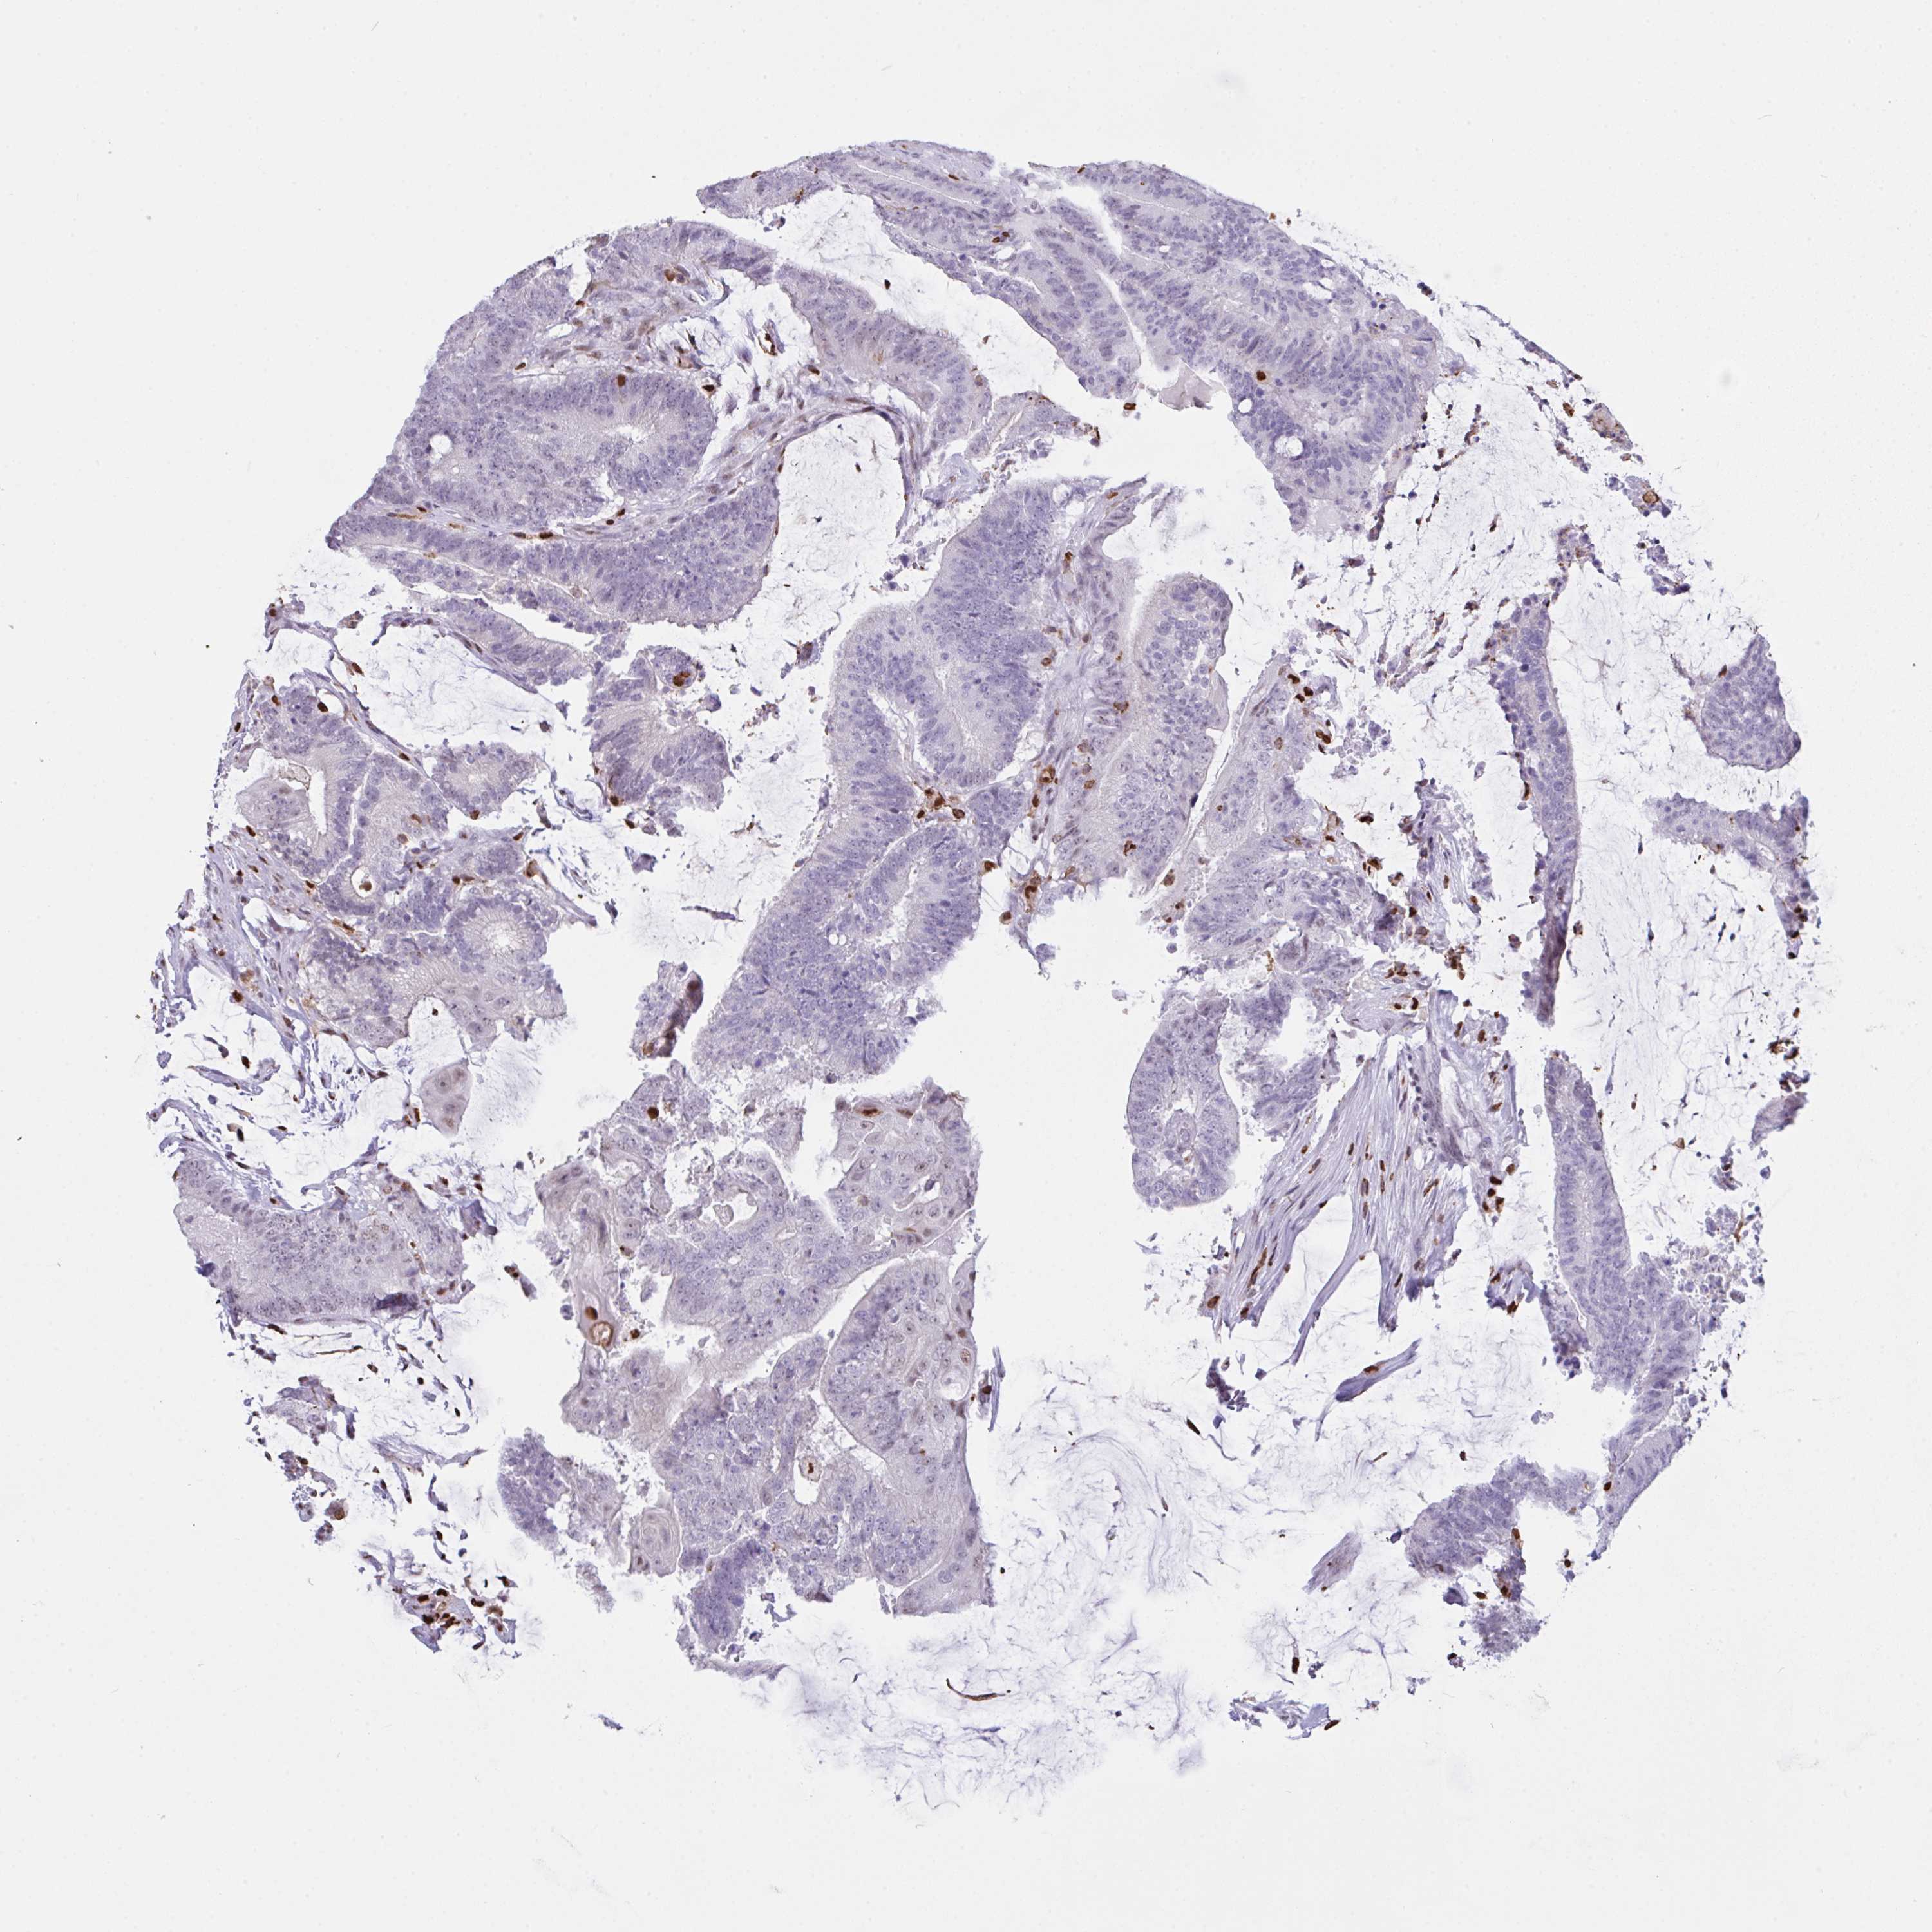

CANCER COLORECTAL CANCER Show tissue menu

Colorectal cancer

Human cancer

Colon adenocarcinoma

Rectum adenocarcinoma